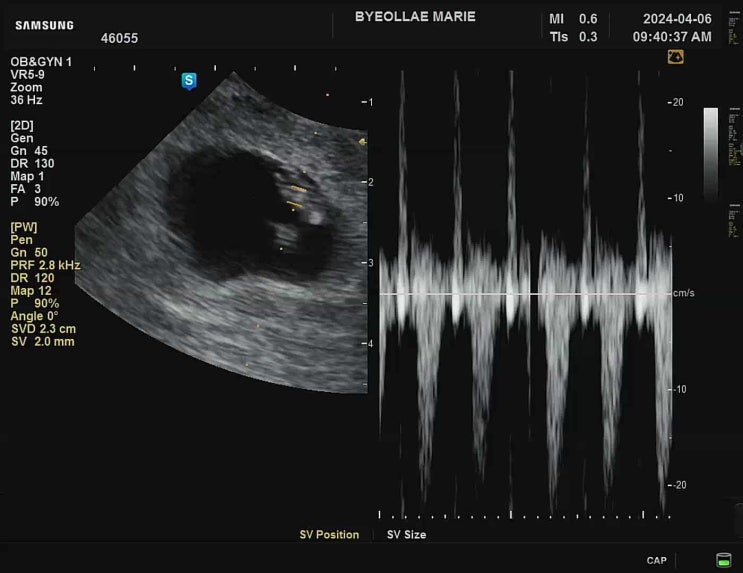

[다낭성 난소 증후군의 자연임신일기 : 26주 검진]입체초음파 + 공포의 임당검사 재검 후기

어느덧 26주 사실 이건 임당 재검 포스팅이다 나는 아무생각없이 26주검진을 갔다 이날 괜히 파워 걱정인형...